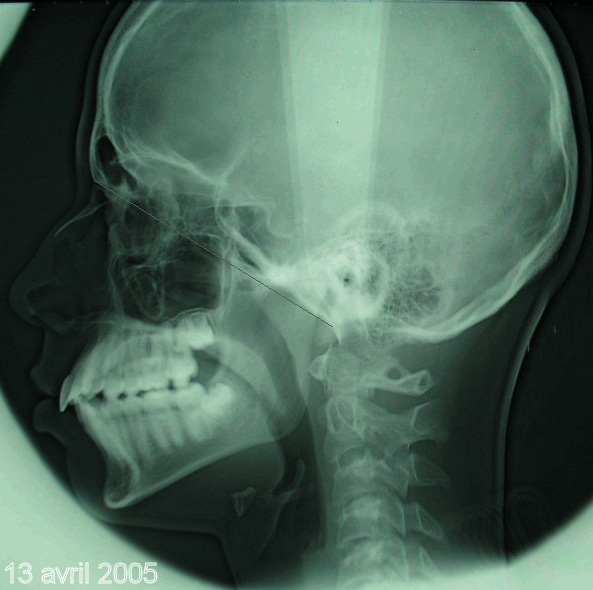

Bonjour, voici les clichés "panoramique" et "télé de profil" du 13 avril 2005 de Florent B. (voir les premiers posts pour comparer juillet 2001 et mars 2004 avec ce 13 avril 2005). J'espère que ces radios vous conviendront parfaitement pour les mesures? Aucun "trucage".

J'attends avec impatience et une grosse pointe de stress votre verdict clair, précis et concis sur l'évolution favorable ou défavorable du cas.

Ne faites pas durer le suspens trop longtemps : je n'en dors plus ! :-)

Je serai heureux si un ODF pouvait mesurer les valeurs 2001 et 2005 sur les téléRx et comparer celles-ci aux valeurs "normales" de vos tables de références.

Tout a été obtenu uniquement par REIOR (approx. x10, successifs) et GAL, cad en l'absence de toute force exogène.

Page précedente, bjc. Teleradiographie 2005.

Peux tu nous donner la longueur réelle Na/Po

comme tracé sur ta télé.

050413teleprofil 1  idegbr - Eugenol

rectification, j'ai tracé Na/Ba.

Longueur ?